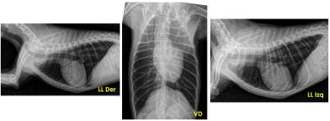

Si nos envías las radiografías torácicas:

Se enviará la proyección LL der/izq y DV/VD, indicando de cual se trata.